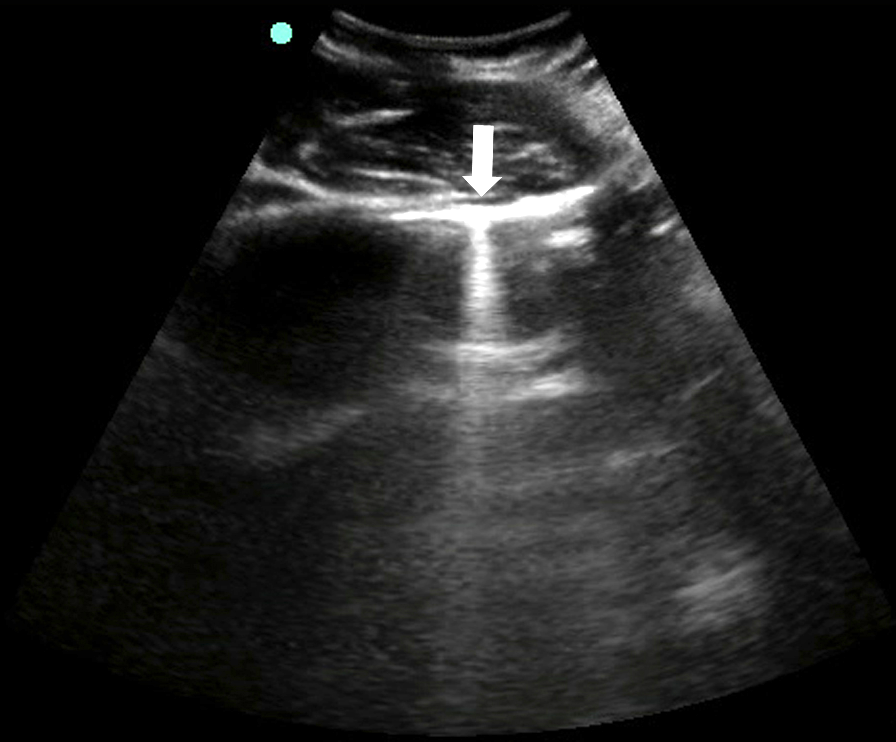

- Mirror image artifact60

- Sound waves reflect off the highly reflective diaphragm, encounter liver tissue, are reflected back to the diaphragm, and then return to the transducer. Based on the time taken for the sound waves to return to the transducer, the machine incorrectly assumes that the initial beam traveled along a linear path and reached the liver tissue deep to the diaphragm. The liver is thus mapped falsely in the deeper location.

- Figure 15. Mirror image artifact